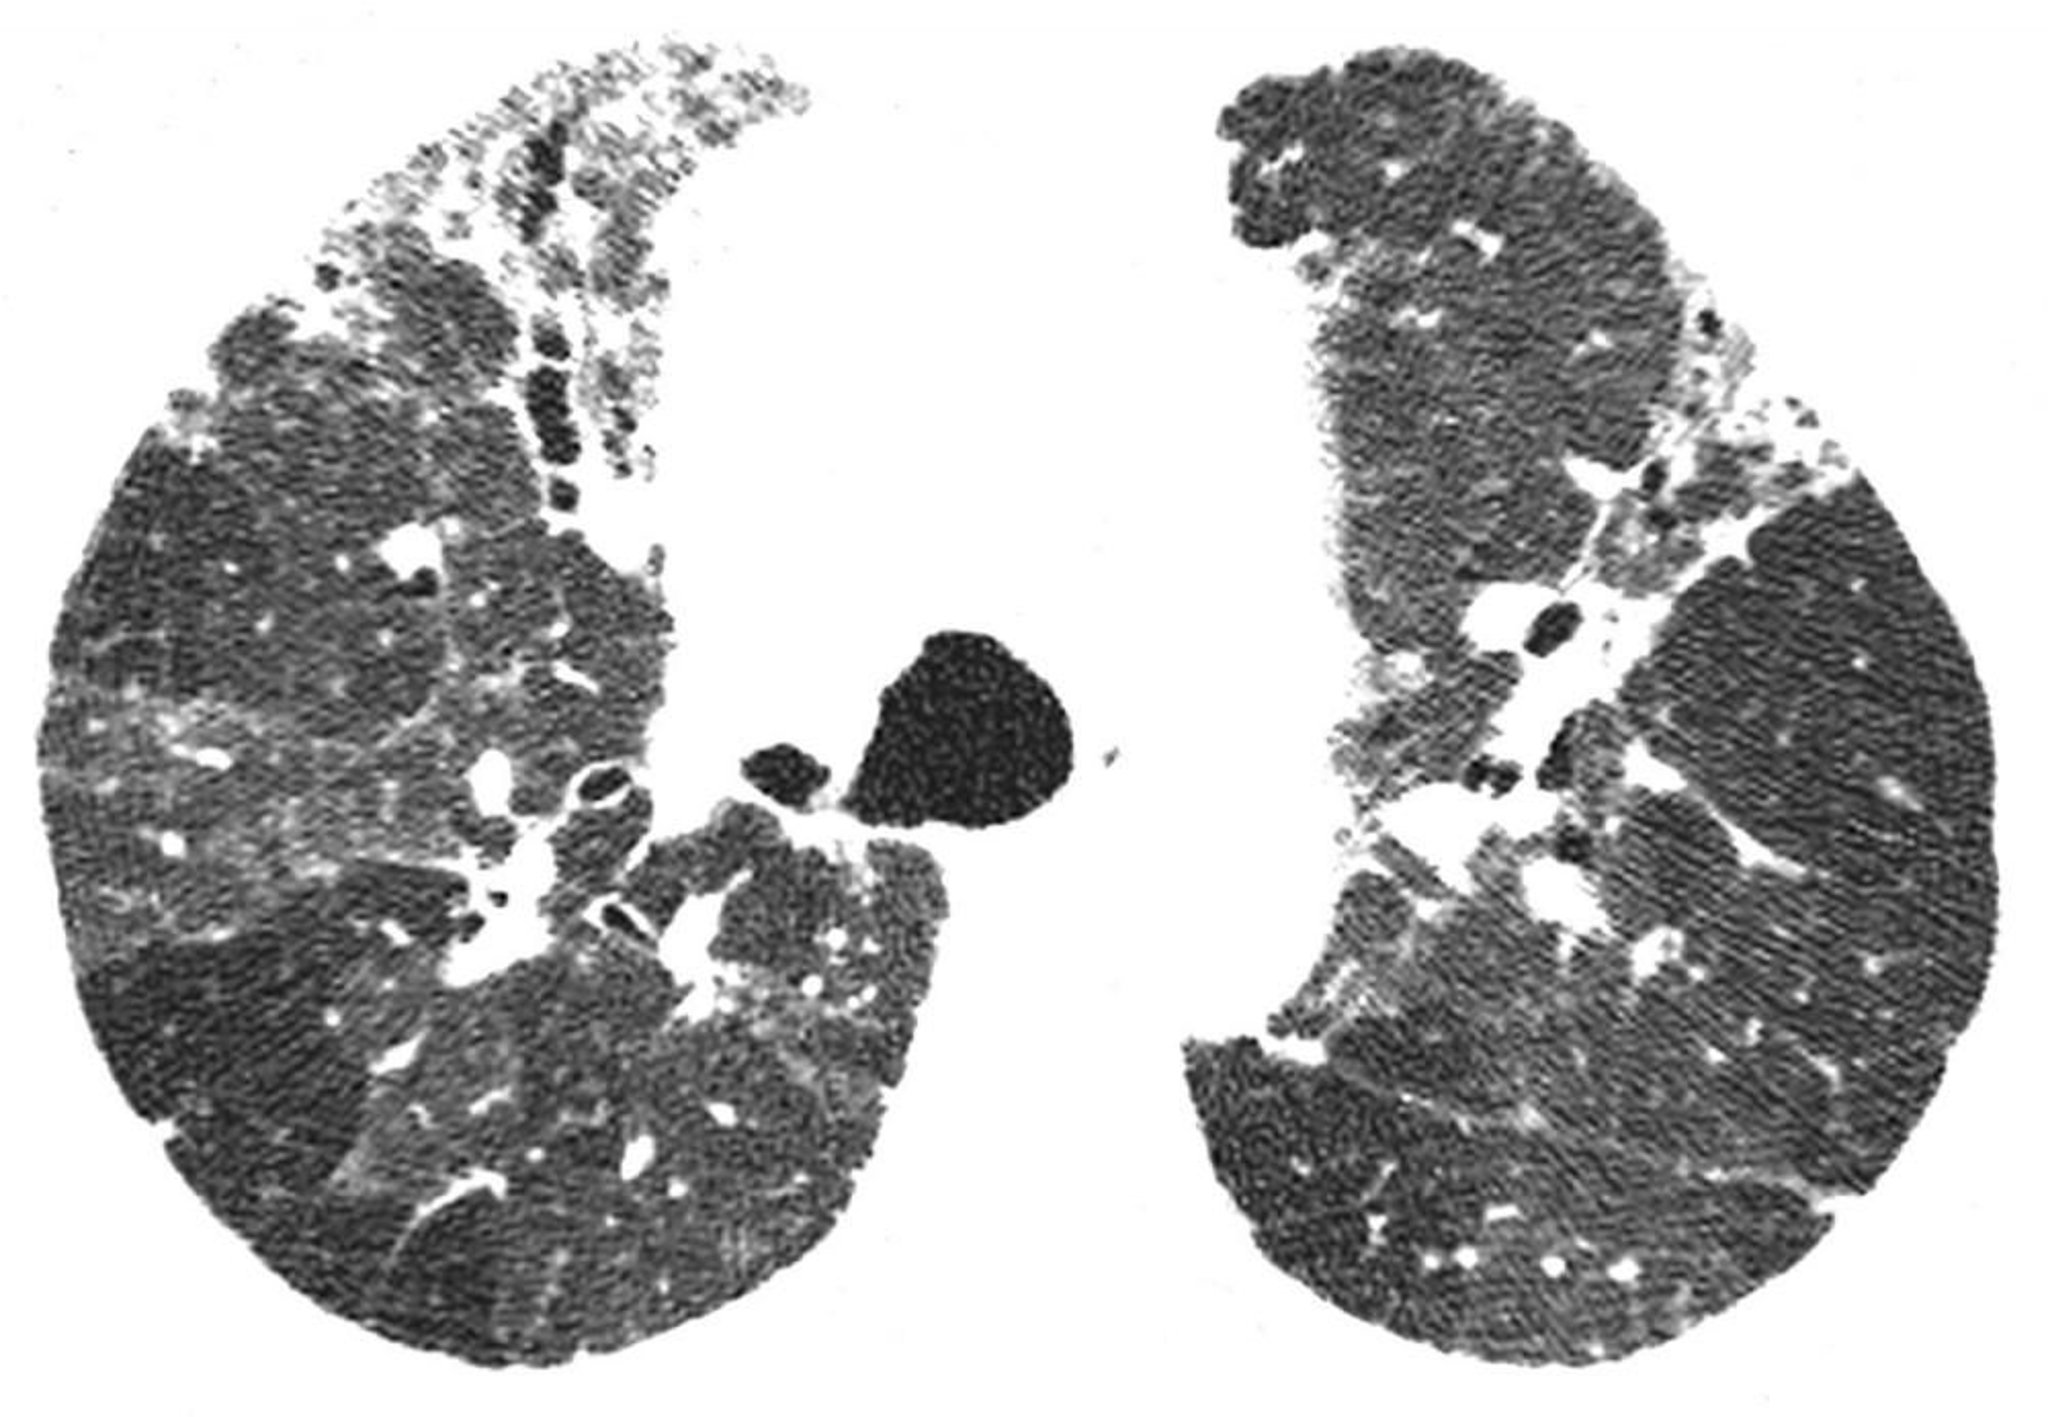

慢性過敏性肺炎

高分解能CTで,不規則網状影および牽引性気管支拡張などの線維化所見がみられる。低吸収領域は,気道が閉塞されている領域と一致する。これら所見の組み合わせにより,過敏性肺炎の診断が示唆される。

Image courtesy of Harold R.Collard, MD.